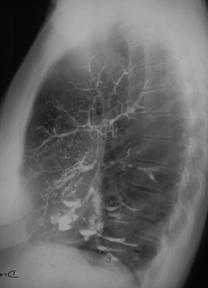

Fig. 14 – Pneumonie lobara superioara dreapta in rezolutie (opacitate sistematizata neomogena, de intensitate mica spre medie, delimitata inferior de mica scizura, ocupand LSD)